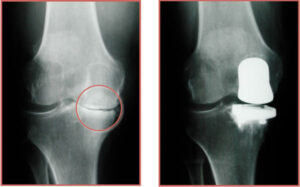

Preoperative Preparation : Patients undergo a thorough evaluation, including imaging tests like X-ray or MRI or Citi scan, blood work and consultations to ensure they are suitable candidates for surgery. Physical preparation, such as strengthening exercises, may also be recommended.

Resurfacing : Damaged bone and cartilage are removed from the femur, tibia and patella. Metal components are then attached to the ends of these bones and a plastic spacer is placed in between them to create a smooth surface for movement.

Total Knee Replacement (TKR), also known as knee arthroplasty, is a surgical procedure that replaces the entire knee joint with an artificial prosthesis to relieve pain and improve function. This procedure is typically recommended for individuals suffering from severe knee pain and limited mobility due to conditions such as osteoarthritis, rheumatoid arthritis or traumatic injury.